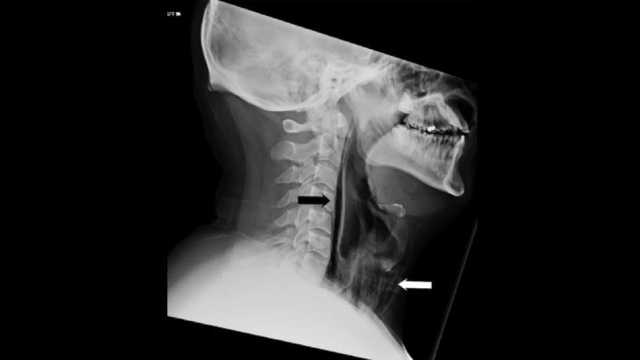

Les tests ont montré des stries d’air dans la région rétropharyngienne et un important emphysème chirurgical dans le cou antérieur à la trachée. En d’autres termes, en essayant de garder son éternuement, il a fait un petit trou dans sa gorge. Heureusement, la perforation était très petite.